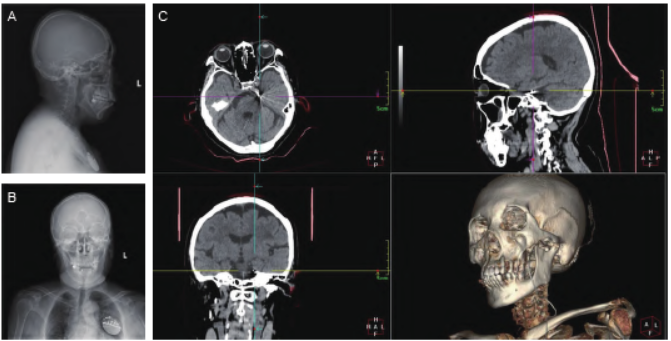

机器人导航引导下沿设定路径穿入穿刺针,见穿透筋膜的突破感时停止进针,拔出针芯,用带刻度穿刺针反复比对术前定位靶点与穿刺针尖完全重合。将带固定翼的自固定4 触点骶神经刺激电极沿穿刺针套管置入Meckel 腔,X 线下调整电极深度,使有效触点贴近三叉神经半月节,保持固定电极于原位不动,拔除穿刺针套管,使固定翼释放固定电极,X 线复查见电极无位移,临时包扎手术切口。

电极导线与脉冲发生器连接,测试电极阻抗及刺激反应正常后,将脉冲发生器埋于胸部皮下囊袋。逐层缝合面部及胸部切口,无菌辅料包扎。术后24 小时开机VAS 评分下降至1,术后刺激1 周VAS 评分均稳定在1,拆线后出院。术后1、3、6 个月随访:开机刺激时VAS 评分均稳定在1,病人极其满意,暂无电刺激相关不良反应发生。6 个月随访时,病人自诉术后5 个月曾自行停止电刺激时仍有疼痛反复至VAS 评分8。

图2 术后复查X 片及CT 影像验证电极、刺激器位置(A)术后侧位X 片;(B) 术后正位X 片;(C) 术后CT 三维重建